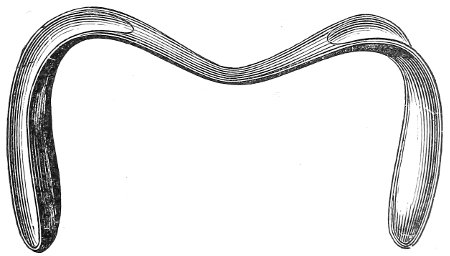

The Vaginal Speculum.—The speculum is an instrument through which a visual examination is made of the vagina, the external os uteri, and the vaginal cervix. A 29 great number of specula have been invented. At the present day the best two instruments of this class are the bivalve speculum, such as Goodell’s (Fig. 6), and the duck-bill speculum (Fig. 7), or perineal retractor, invented by Sims.

Fig. 7.—Sims’ speculum.

The Sims speculum enables us to make the most thorough inspection of the vagina, the vaginal vault, and the vaginal cervix. The Sims speculum is merely a hook or retractor for the perineum, and may be introduced with the woman in the dorsal position, the Sims position, or the genu-pectoral position. If the Sims speculum is introduced in the dorso-sacral position, it is necessary to hold forward the anterior vaginal wall in order to obtain a view of the cervix.

Fig. 10.—The Sims position.

The Sims position, which is also called the latero-abdominal position, is shown in Fig. 10. The woman is placed on the bed or table upon her left side. The side of the face is upon the pillow; the left arm is behind the back, so that the left breast rests upon the table. The thighs are flexed upon the abdomen at an angle of about 90° to the trunk. The right thigh is more flexed than the left, so that the right knee may touch the table above the left knee. The legs are flexed on the thighs. In this position there is a tendency for the intestines, following the force of gravity, to fall from the pelvis, 32 and for the uterus and other pelvic viscera to be drawn up. When the perineum is retracted with the blade of the Sims speculum, air will enter the vagina and the vaginal slit will become distended (Fig. 11). To facilitate inspection of the cervix it is usually necessary also to push forward the anterior abdominal wall by some kind of depressor, such as the one shown in Fig. 8.

Fig. 11.—The cervix uteri exposed with the Sims speculum.

The Sims speculum, with the woman in the dorsal, the Sims, or the knee-chest position, is the most useful instrument by which to expose the cervix uteri for any of the minor operations of gynecology. The manipulations of the operator are not hampered by working between metal walls.